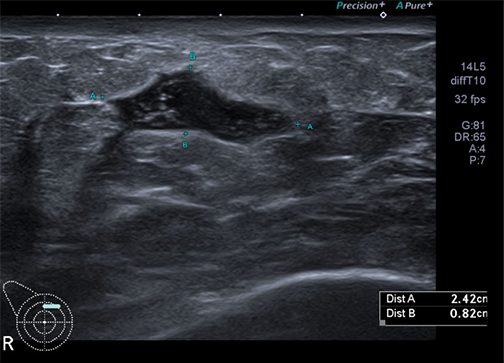

이 질환이 임상적으로 중요한 이유는 증상과 초음파 소견이 유방암과 유사하기 때문입니다.

때문에 초기 진단 시 반드시 조직검사가 필요합니다.